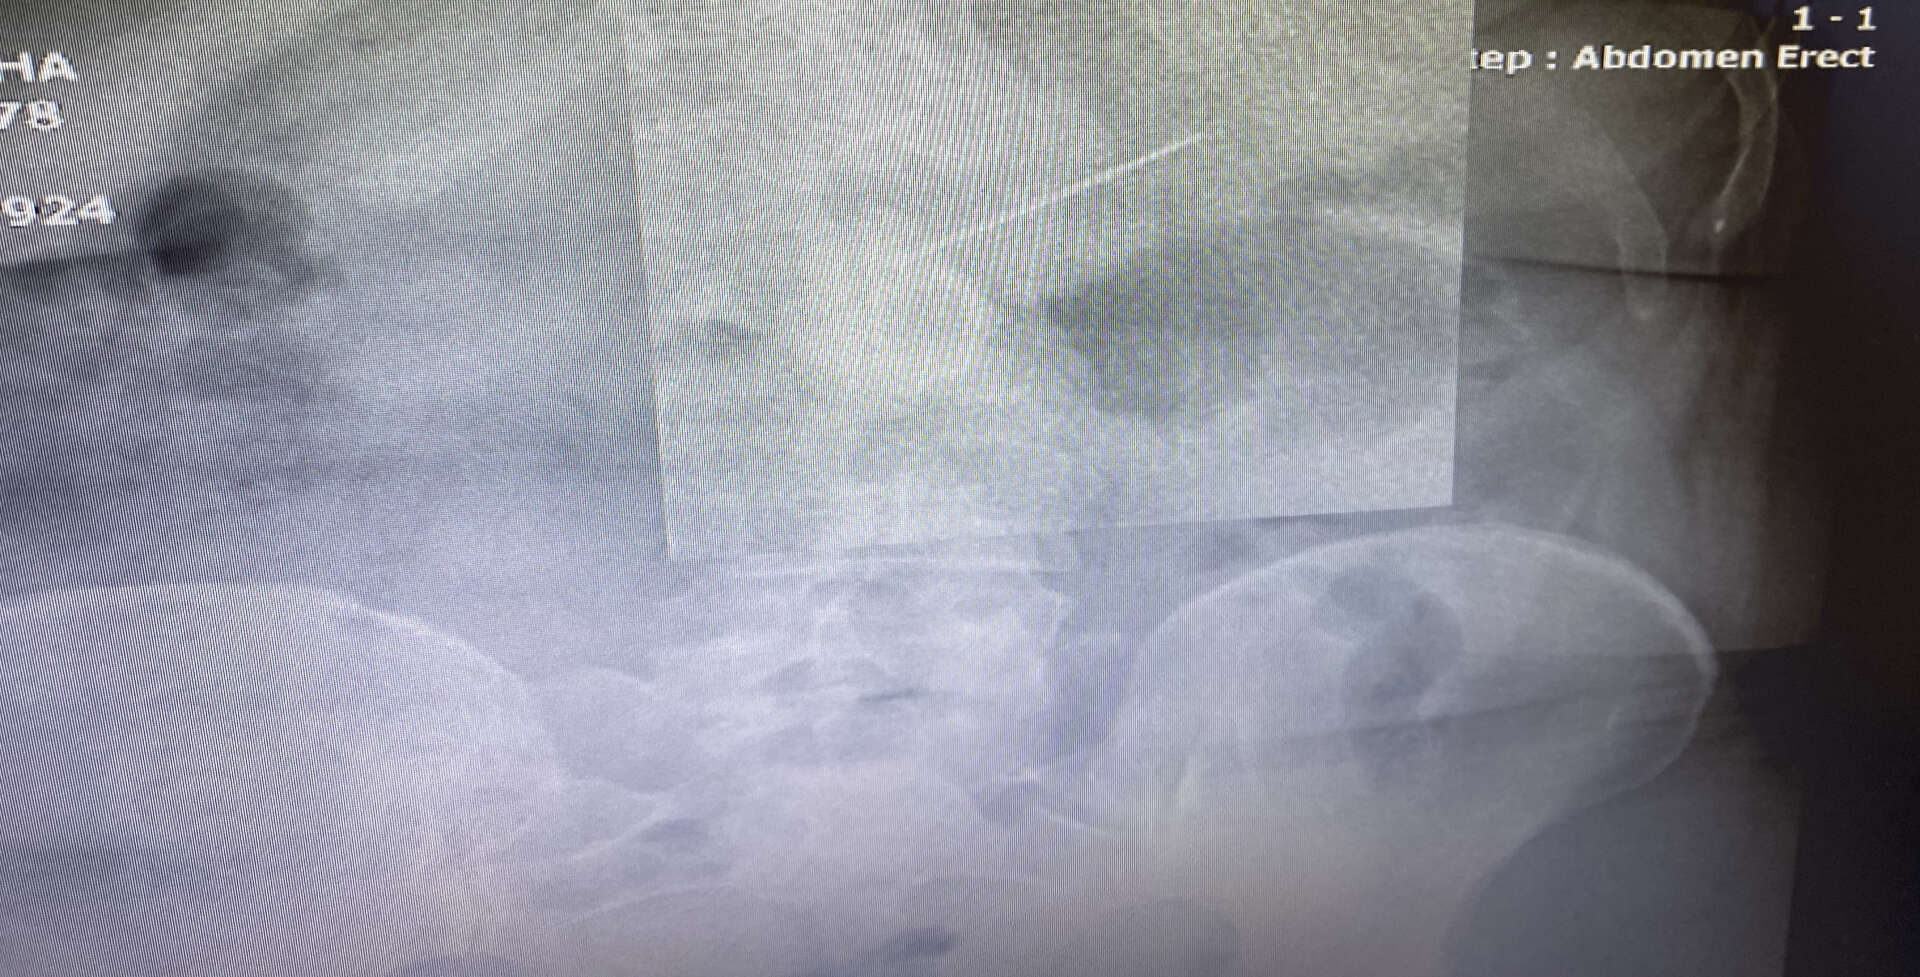

Gaziosmanpaşa’da yaşayan 2 çocuk annesi 45 yaşındaki Semiha Keçeci, iddiaya göre 23 Ocak'ta acelesi olduğu için başörtüsünü düzeltirken ağzına aldığı iğneyi hapşırınca yuttu. Yaklaşık 3,5 santimlik iğneyi yuttuğunu anlayan kadın şok olurken bir anda acı içinde kaldı. Başakşehir Çam ve Sakura Şehir Hastanesi acil servisinde tedavi altına alınan kadına hemen film çekildi.

Toplu iğnenin mideye ulaştığı belirlenirken, gerçekleştirilen endoskopik işlemle hastanın midesindeki iğne olduğu noktadan alındı. Keçeci, rahat bir nefes alırken, Başakşehir Çam ve Sakura Şehir Hastanesi Genel Cerrahi Bölümü’nden Op. Dr. İsmail Çalıkoğlu, gerçekleştirilen tedaviye ilişkin bilgi verdi. Mideye ulaşan iğne filmdeki görüntüsüyle gözler önüne serilirken, Op. Dr. Çalıkoğlu, özellikle çocuklarda yabancı cisim yutmalarına karşı uyardı.